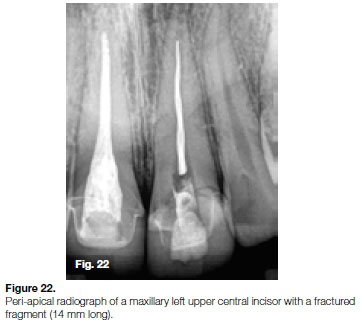

Case report 4

The patient, a 21 year old male presented with a fractured rotary file in his maxillary left upper central incisor. The fragment (14mm long) was located approximately 4mm apically from the cemento-enamel junction at the coronal aspect extending apically to about 5 mm from the apical foramen (Figure 22). Under 15x microscope magnification, the fractured instrument was clearly visible in the canal (Figure 23).